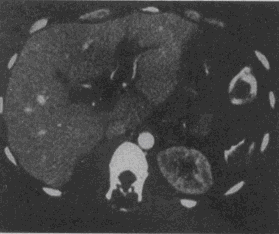

3.男,46歲,脾臟術后3天,右上腹痛,CT掃描如圖,最可能的診斷是

A.肝臟正常、脾臟術后改變

B.肝門脈血栓形成,脾臟術后改變

C.肝內膽管囊腫

D.膽總管下端結石

E.膽管細胞癌

正確答案:B解題思路:門脈管腔增大,管腔內可見軟組織影,未見強化,未見脾臟。